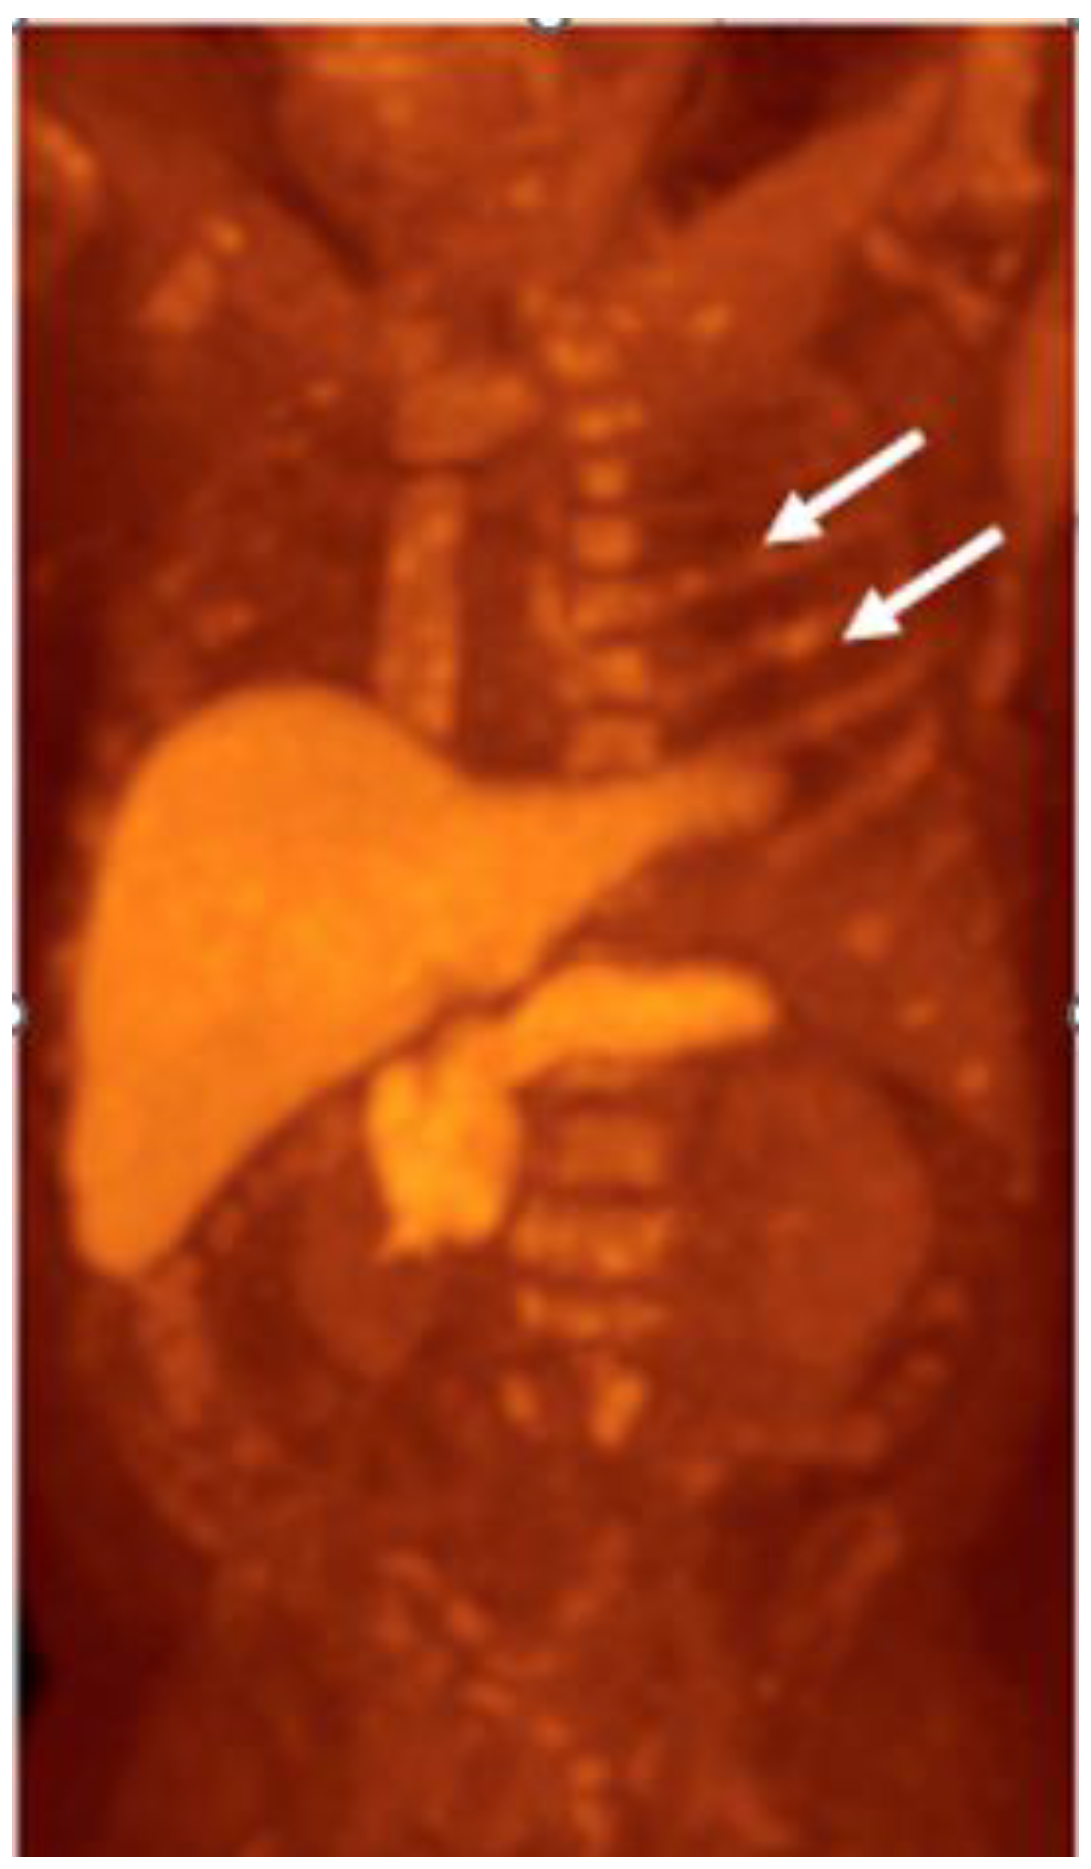

Detection of Loco-Regional Disease and Distant Metastases

- Barbosa, F.G.; Queiroz, M.A.; Nunes, R.F.; Viana, P.C.C.; Marin, J.F.G.; Cerri, G.G.; Buchpiguel, C.A. Revisiting Prostate Cancer Recurrence with PSMA PET: Atlas of Typical and Atypical Patterns of Spread. Radiographics 2019, 39, 186–212. [Google Scholar] [CrossRef]